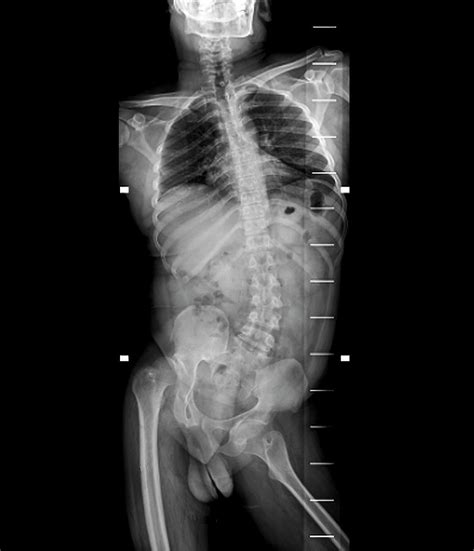

a. Spinal Polio

Spinal polio is the most common form of paralytic polio. It occurs when the virus attacks motor neurons in the spinal cord, which control limb muscles. This can lead to paralysis in one or more limbs, often asymmetrically. Symptoms typically begin with fever, headache, muscle pain, and then sudden muscle weakness or paralysis.